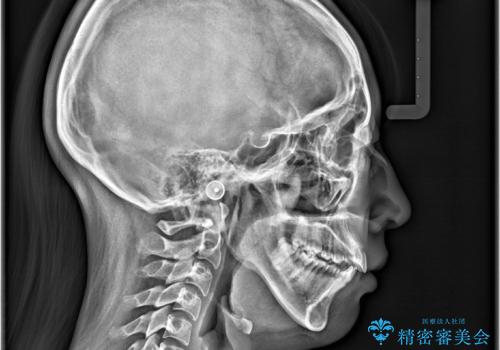

- 歯のデコボコと右上2番の歯の形が気になることを主訴に来院された患者様です。

軽度の叢生(凸凹)であったため、インビザラインのライトパッケージを用いて歯並びを改善しました。その後、右上2番はオールセラミッククラウンにより形態を回復し、審美性を向上させました。